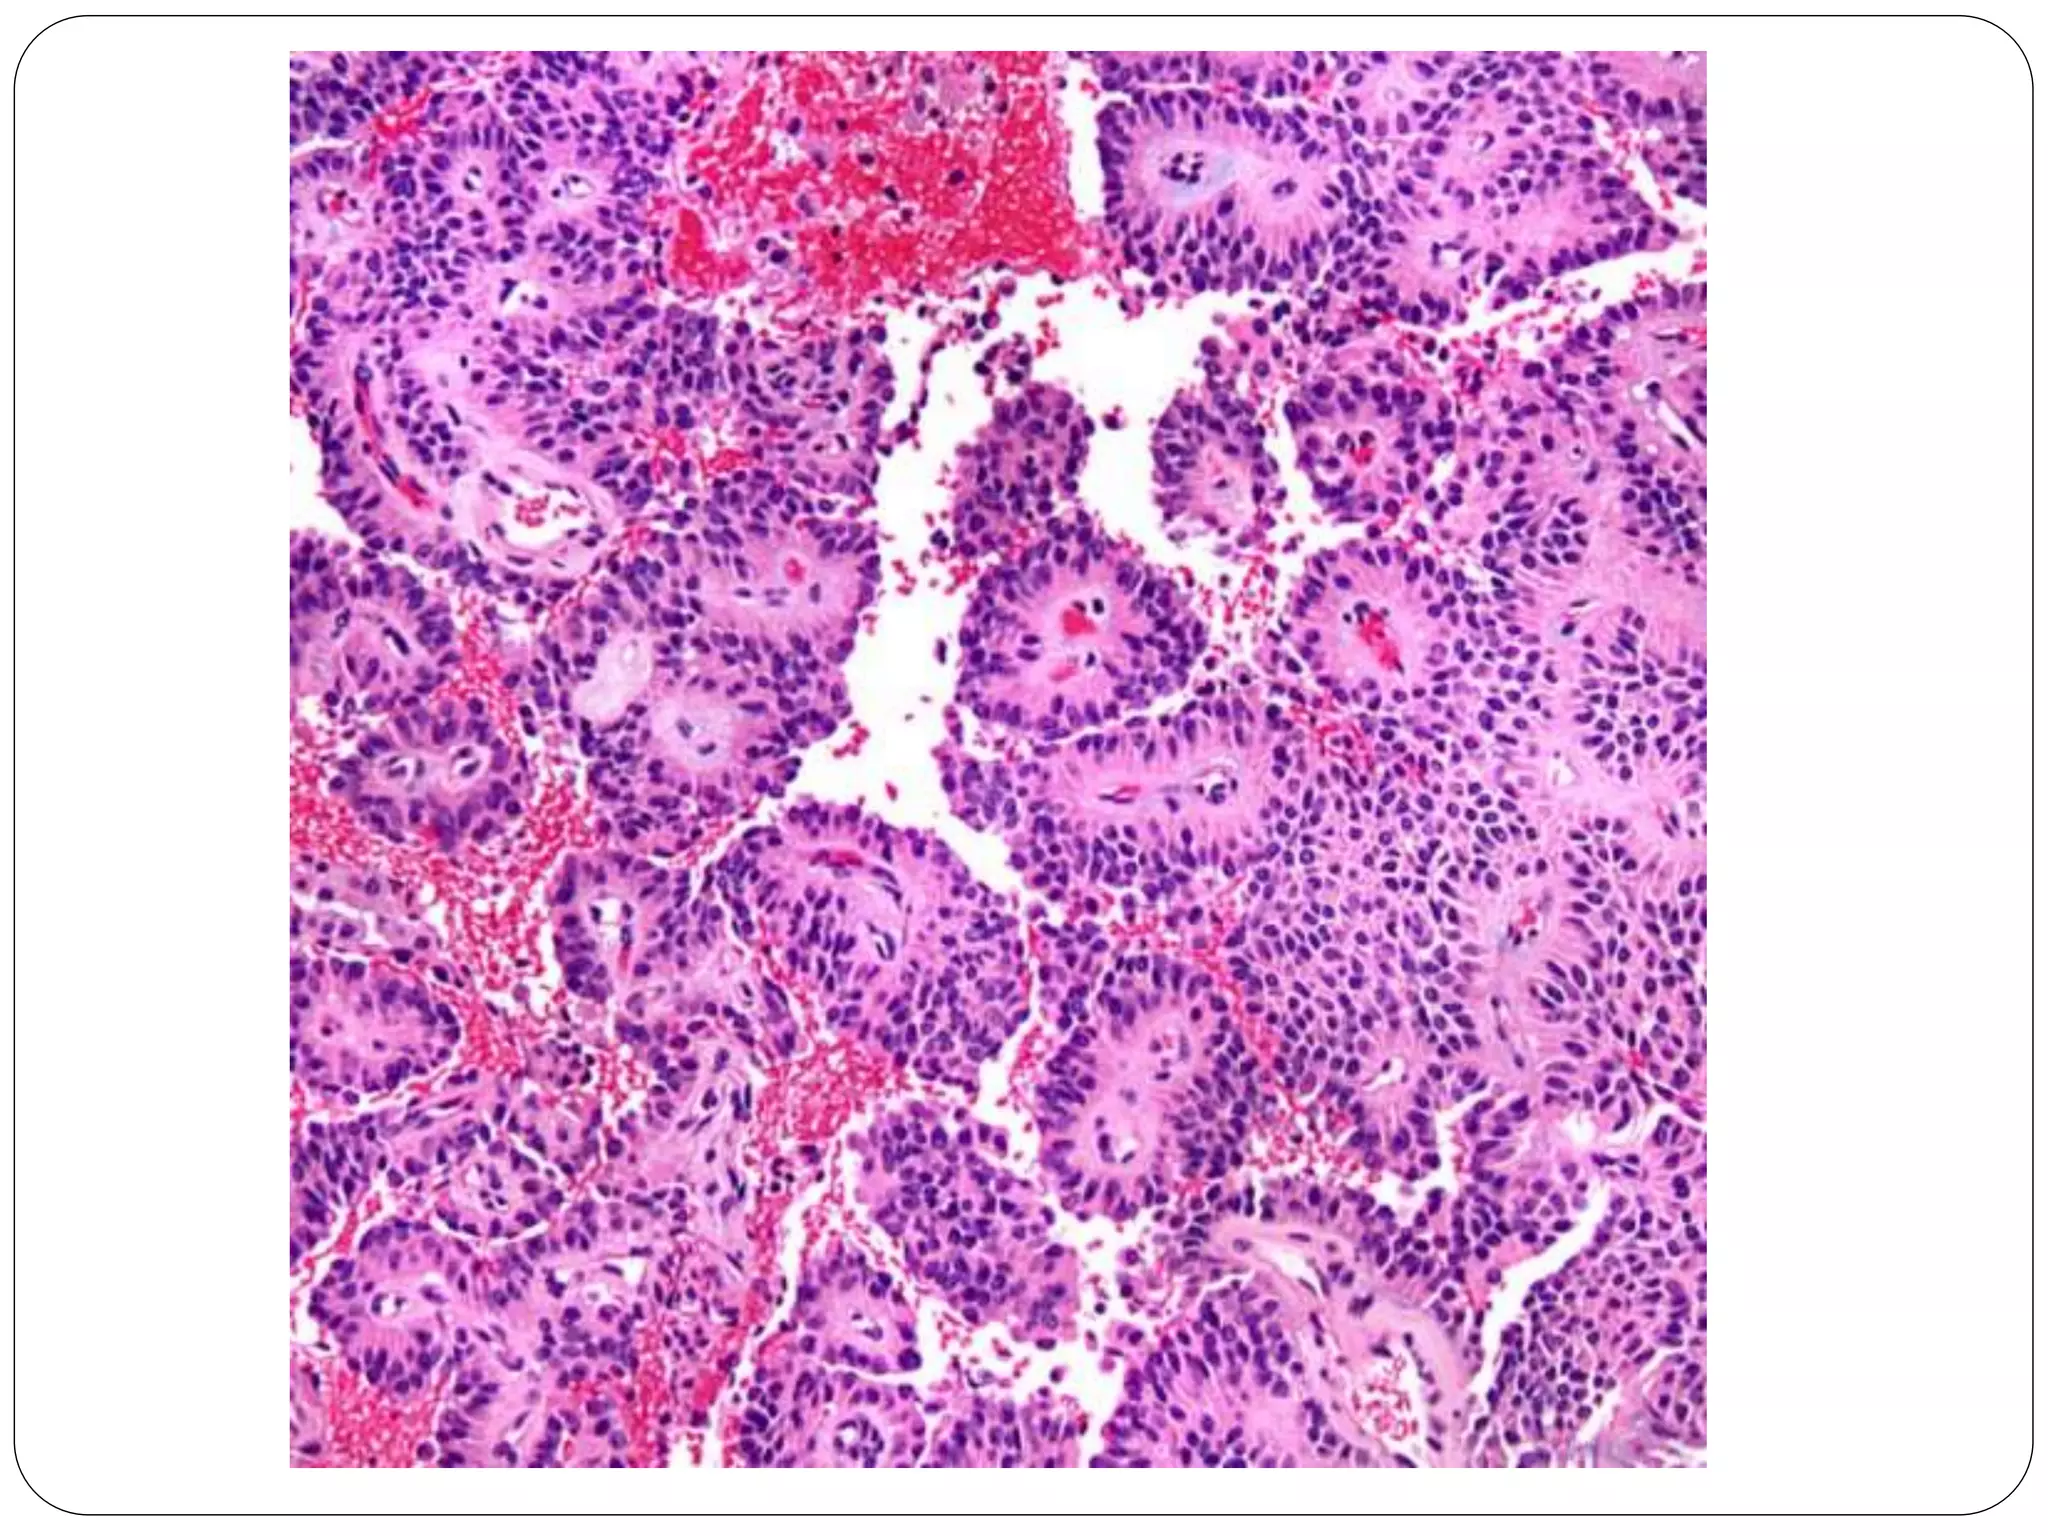

• #13 Solid sheets of tumor cells become dyscohesive and result in a characteristic pseudopapillary appearance with a central fibrovascular-like core surrounded by neoplastic cells.

• #14 The delicate vessels can have myxoid stroma or may be hyalinized.